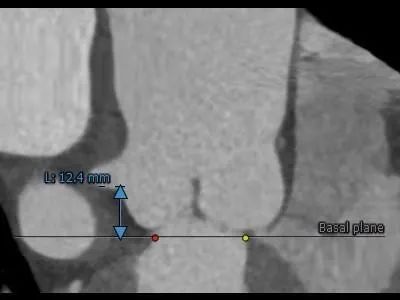

主动脉根部测量:

Type 0 型二叶式主动脉瓣,横位心

冠脉开口高度可,切线角度测量,左窦瓣叶长于左冠开口下缘